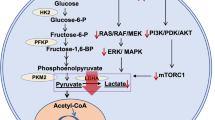

Impact of BTK inhibition on cell metabolism

Next, we performed LC‒MS-based metabolomics using two cell lines with moderate (REC-1) and high (MCL-RL) IBR sensitivity. We performed untargeted steady-state polar metabolite profiling on these two cell lines and treated them with DMSO alone or with IBR-DMSO for 24 h. LC‒MS identified 166 and 185 polar metabolites in REC-1 and MCL-RL cells, respectively. Using a p-value < 0.05 and a fold change (FC) cutoff of ± 1.5, we selected 77 metabolites from REC-1 and 51 from MCL-RL for further pathway analysis. The IBR impaired a large spectrum of metabolic pathways in the two MCL cell populations, including pyrimidine and purine synthesis; the tricarboxylic acid (TCA) cycle; the pentose shunt; glycolysis; and the synthesis of the amino acids alanine, aspartate, and glutamate (Fig. 2a, and Figs. S6, and S7). Among the affected metabolic pathways, glycolysis/pyruvate metabolism/Warburg effect and alanine metabolism attracted our attention because we were able to detect the related metabolites lactate and alanine in intact cells using 1H MRS imaging [6]. Fig. S6 also shows the accumulation of choline, another metabolite detectable by in vivo 1H MRS as part of the total choline complex, which is typically dominated by phosphocholine [16].

BTK inhibition-mediated suppression of metabolic pathways and extracellular lactate flux. a Impact of BTK inhibition on cell metabolism in sensitive MCL cells. The highlighted metabolic pathways affected in REC-1 and MCL-RL cells by their treatment with IBR have been identified by LC–MS and metabolome-targeting bioinformatics. b Impact of BTK inhibition in MCL cells on extracellular lactate. The depicted four MCL cell lines that differ in their sensitivity to BTK inhibition (Fig. 1a) were cultured with 500 nM of BTK inhibitor IBR and examined at the indicated time points for lactate concentration by using YSI 2300 biochemical analyzer. All experiments were performed in triplicates and the data are presented as mean ± SEM. with the p-values of statistical significance indicated

Notably, the impairment of glycolysis and amino acid metabolism directly correlated with the BTK inhibition-mediated suppression of the mRNA expression of the key enzymes involved in these processes and the related oxidative phosphorylation, as observed in the REC-1 and MCL-RL cells (Supplemental Tables S1 and S2, respectively). The above findings indicate that BTK induces the expression of these metabolic enzymes and that the BTK inhibition-mediated decrease in the synthesis of lactate (a product of mainly glycolysis) and alanine (an indicator of amino acid metabolism) is due, at least in part, to the suppression of the expression of genes encoding enzymes involved in metabolism.

Impact of BTK inhibition on glucose and amino acid metabolism related to cell respiration

To gain deeper insight into BTK inhibition-induced changes in glucose metabolism in MCL cells, we performed Seahorse XF Glyco Stress Tests. In these assays, the basal proton efflux rate (PER) was determined, followed by a glucose pulse to increase glycolysis and subsequent treatment with oligomycin to determine the total glycolytic capacity. Finally, a pulse with 2-deoxy-D-glucose (2-DG) was used to evaluate the glycolytic reserve. The highly and moderately BTK inhibition-sensitive MCL-RL and REC-1 cells, respectively, displayed markedly impaired glucose utilization when treated with either ACP-196 (Fig. 3a, upper row) or IBR (Fig. S9, upper row). Conversely, the poor BTK inhibition-sensitive JeKo-1 cells showed a limited decrease in glucose utilization (Fig. 3a, upper row), whereas the resistant MCL-SL cell line did not show noticeable changes in glucose utilization (Fig. 3a and Fig. S9, upper rows). These findings further functionally link BTK with glycolysis and strongly support the notion that lactate, the end-product of glycolysis, is a highly reliable marker of BTK inhibition.

Metabolic impairment and 1H MRS-detectable biomarkers of BTK inhibition. a Effect of BTK inhibition on glucose metabolism and mitochondrial respiration. The index MCL cell lines were exposed for 48 h to 250 nM of BTK inhibitor ACP-196 or the drug vehicle and comprehensively tested for glucose metabolism (upper row) and mitochondrial respiration (lower row) by Seahorse-based examination. The depicted difference between BTK inhibitor-treated vs. control cells at the various stages of the tests were at least: *p < 0.05, **p < 0.001, and ***p < 0.0001. b Impact of BTK inhibition in MCL cells on lactate, alanine, and total choline percent change measured by high-resolution 1H MRS. All data are displayed as mean ± SEM, with the statistically significant p-values of the difference between BTK inhibitor-treated vs. controls also depicted

To evaluate the effect of BTK inhibition on oxygen consumption, which mainly reflects amino acid metabolism-driven mitochondrial respiration, we performed a Seahorse XF Mito Stress Test, in which basal respiration was assessed by inhibition, maximal respiration induction, and spare respiration capacity evaluation. The highly sensitive MCL-RL cells with BTK inhibition displayed a markedly diminished oxygen consumption rate (OCR) in response to BTK inhibition by either ACP-196 (Fig. 3a, lower row) or IBR (Fig. S9, lower row). In contrast, moderately (REC-1)- and poorly (JeKo-1)-sensitive and resistant (MCL-SL) cells displayed essentially no decrease or even a mild increase in the OCR in response to BTK inhibition (Fig. 3 lower row and Fig. S9), suggesting that the maintained amino acid-dependent mitochondrial respiration contributes to the limited sensitivity to BTK inhibition. Marked inhibition of both glycolytic and glutaminolysis flux by IBR in BTK inhibition-susceptible MCL-RL cells as well as of glycolytic flux but not glutaminolysis flux in poorly sensitive JeKo-1 cells (Fig. S10), further supporting this notion.

Although the central role of BTK in B-cell receptor (BCR)-driven cell signaling is well established [3, 4, 18,19,20,21], our results demonstrate a novel and critical role of BTK in cell metabolism, given that BTK inhibition affects key metabolic pathways, including pyrimidine and purine synthesis, the TCA cycle, glycolysis, and pyruvate and alanine metabolism, in MCL cells (Fig. 2a). While the BTK inhibition-mediated impaired supply of DNA nucleotides affects the proliferation rate (Fig. 1a) and cell cycle progression (Fig. 1b) of MCL by directly preventing DNA synthesis, the other affected metabolic pathways are critical for generating energy to essentially support all key cell functions. These combined findings strongly suggest that the inhibition of cell metabolism is an important, if not critical, mechanism responsible for the efficacy of BTK inhibitors as therapeutic agents in lymphoma.